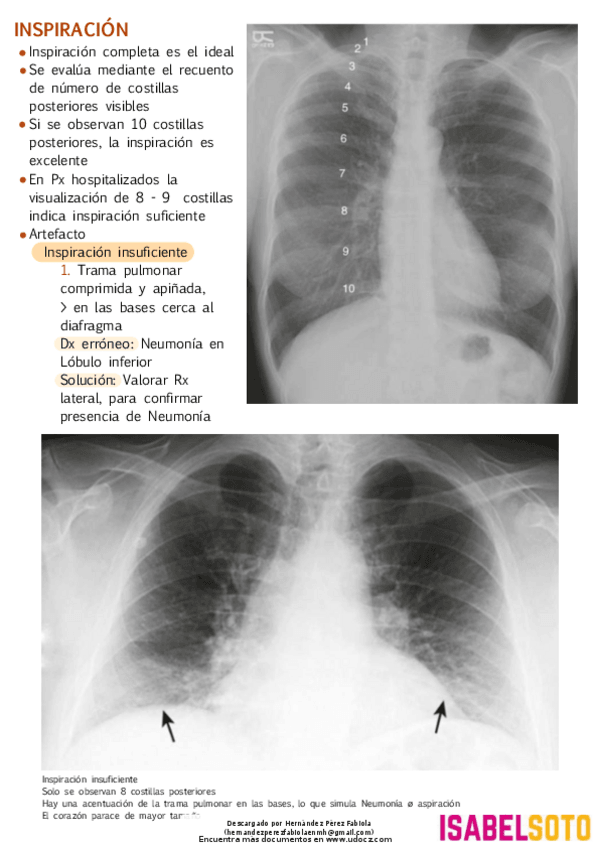

He publicado nuevos apuntes de 3º Radiología Clínica: ASPECTOS-PARA-DETERMINAR-SI-EL-TORAX-ES-ACEPTABLE.pdf